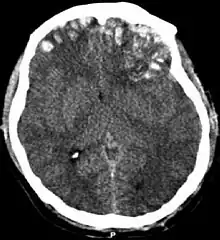

| CT scan showing cerebral contusions, hemorrhage within the hemispheres, and subdural hematoma. There is also displaced skull fracture of left transverse parietal and temporal bones.[2] | |

One type of focal injury, cerebral laceration, occurs when the tissue is cut or torn.[37] Such tearing is common in orbitofrontal cortex in particular, because of bony protrusions on the interior skull ridge above the eyes.[31] In a similar injury, cerebral contusion (bruising of brain tissue), blood is mixed among tissue.[23] In contrast, intracranial hemorrhage involves bleeding that is not mixed with tissue.[37]

Hematomas, also focal lesions, are collections of blood in or around the brain that can result from hemorrhage.[11] Intracerebral hemorrhage, with bleeding in the brain tissue itself, is an intra-axial lesion. Extra-axial lesions include epidural hematoma, subdural hematoma, subarachnoid hemorrhage, and intraventricular hemorrhage.[38] Epidural hematoma involves bleeding into the area between the skull and the dura mater, the outermost of the three membranes surrounding the brain.[11] In subdural hematoma, bleeding occurs between the dura and the arachnoid mater.[23] Subarachnoid hemorrhage involves bleeding into the space between the arachnoid membrane and the pia mater.[23] Intraventricular hemorrhage occurs when there is bleeding in the ventricles.[38]